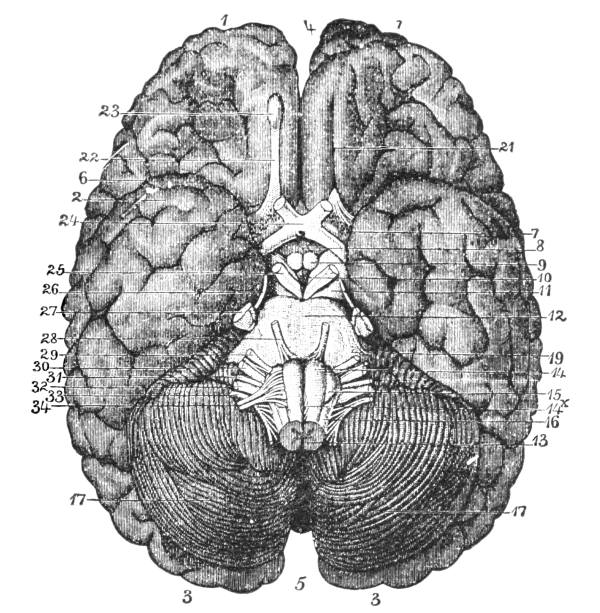

The Cerebrum, 75—The Cerebellum, 78—Pons Variolii, 78—Medulla Oblongata, 78—Spinal Cord, 79—Brain-centers, 81—Motor Tract, 82—Sensory Tract, 82—Reflex Action, 83—Cranial Nerves, 83—Spinal Nerves, 84—Brachial Plexus, 85—Sacral Plexus, 85—The Sympathetic System, 87—The Sympathetic Nerves, 87. |